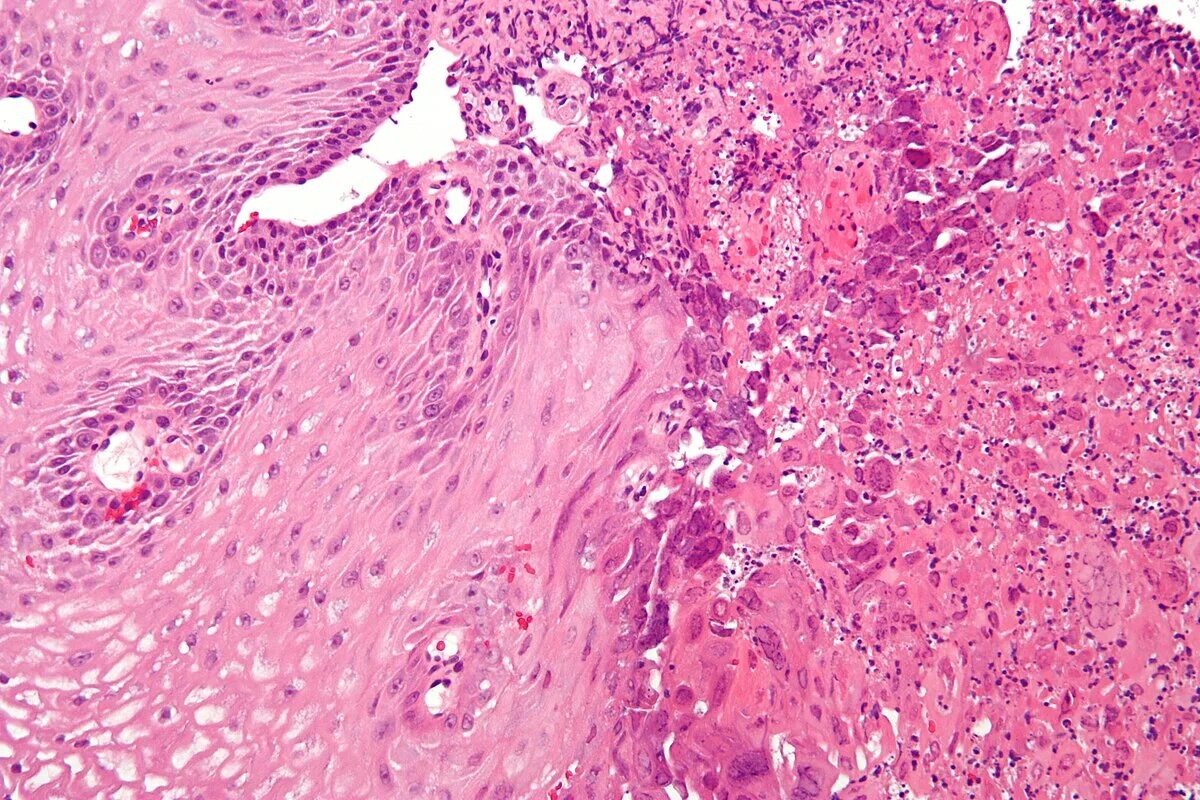

Раздражение пищевода